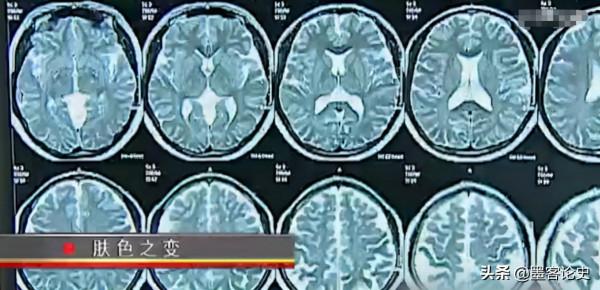

在經過醫生的檢查後,突然發現,在她的腦子中,有一個像蝌蚪一樣的陰影。

而這種東西像是瘤體,從片子上看,這已經長到了顱底斜坡上。

果不其然,呂美琴真的是腦子裡出現了問題,那麼這個瘤體主要是帶來什麼因素呢?

醫生給出了一個專業性的解釋:

“這個像蝌蚪一樣的垂體瘤,主要就是給身體發出一些激素和指令。而這些東西都是錯誤的,因此導致呂美琴腦部的腫瘤讓腎上腺分泌了過多的皮質醇。現在將腎上腺切除了,這個腫瘤就會向其他的部位發出錯誤指令。”